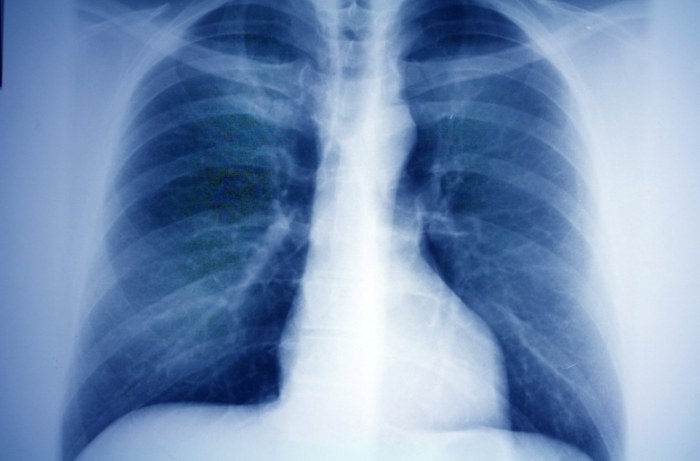

肺部檢查發現毛玻璃結節時,多數屬於毛玻璃結節良性(約60-70%)。毛玻璃結節原因可能與發炎、感染或空氣污染有關,其毛玻璃結節生長速度緩慢者通常預後較佳。部分患者透過抗生素治療可使毛玻璃結節消失,若持續增大則需考慮毛玻璃結節治療(如手術切除)。定期追蹤是管理關鍵!

肺部檢查發現毛玻璃結節病灶時,需定期進行毛玻璃結節追蹤(建議3-6個月複查)。毛玻璃結節原因可能與發炎、感染或早期病變有關,其毛玻璃結節生長速度緩慢者多屬良性。若出現毛玻璃結節轉移跡象則需積極介入,毛玻璃結節治療方式包含手術切除或標靶藥物。早期發現是預後關鍵!

肺結節治療該怎麼選擇?肺結節基本信息、治療方法、中醫與西醫治療、治療後注意事項、患者心態等,這些都是患者需了解的重點。肺結節治療方法包括手術、放療、中醫治療等,治療後需定期檢查、保持良好生活習慣。中醫治療強調調理身體,西醫則注重精確治療。患者保持積極心態有助於康復。